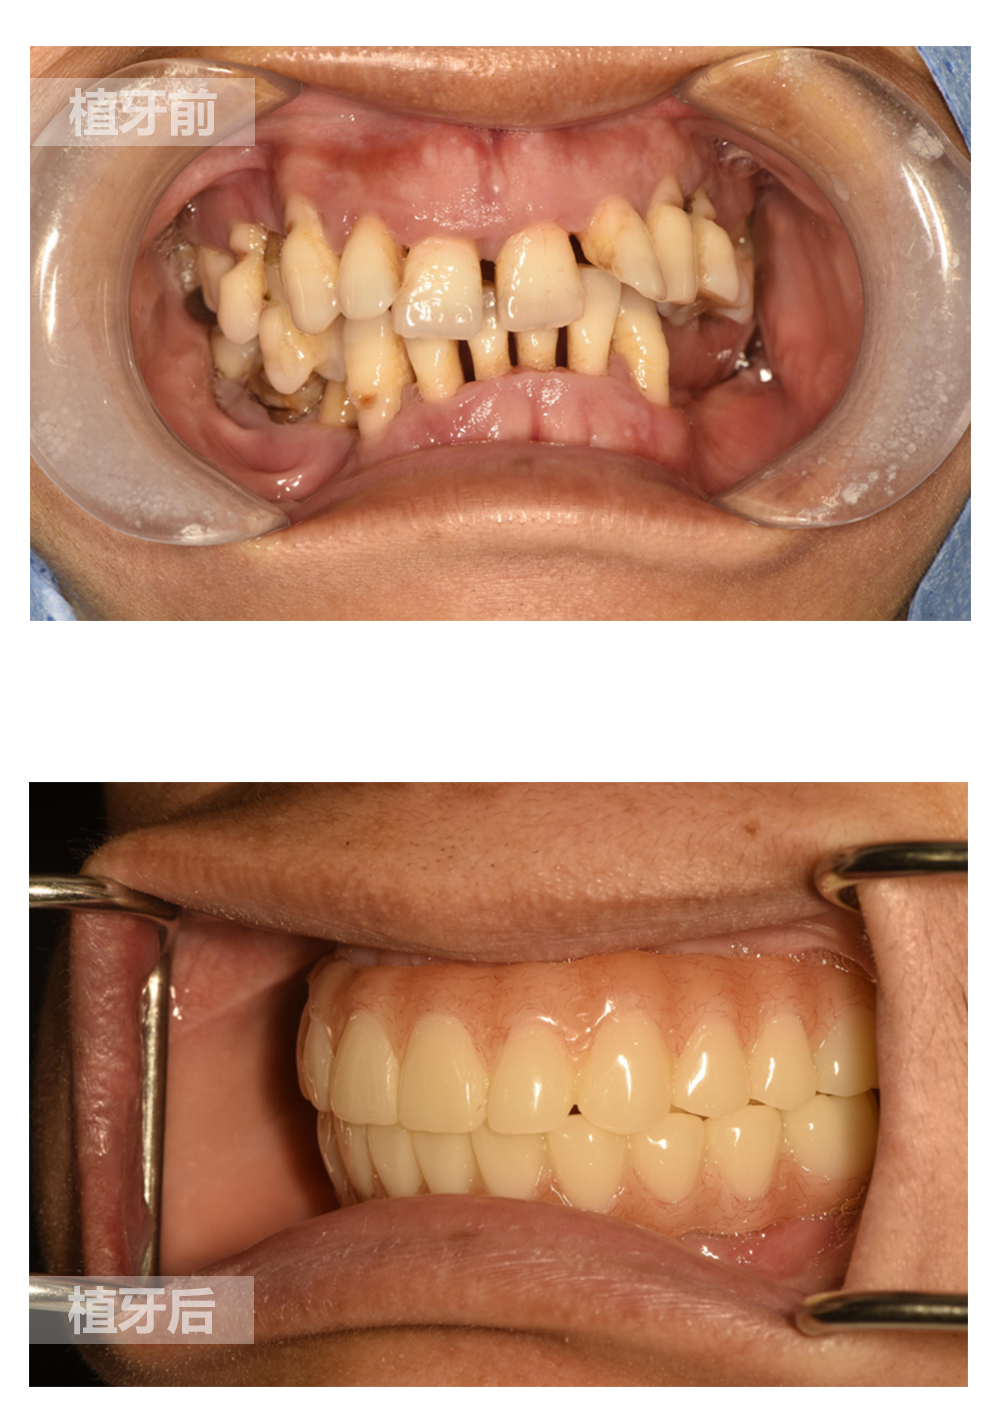

种植牙是在牙骨内植入人造牙根(即种植体),用来支持人造牙冠(义齿)。

种植牙要能够稳固地固定在颌骨内并将支持人造牙冠(义齿)。种植体是使用钛金属、钛合金或陶瓷制作的小螺钉 – 这些材料都具有很好的生物相容性,被人体接受。同时,钛金属与人类骨骼之间的结合效果十分优异。

局部麻醉状态下,进行种植体植入手术。种植体与骨牢固结合愈合后,人工牙根将为上部裸露牙冠提供支撑。